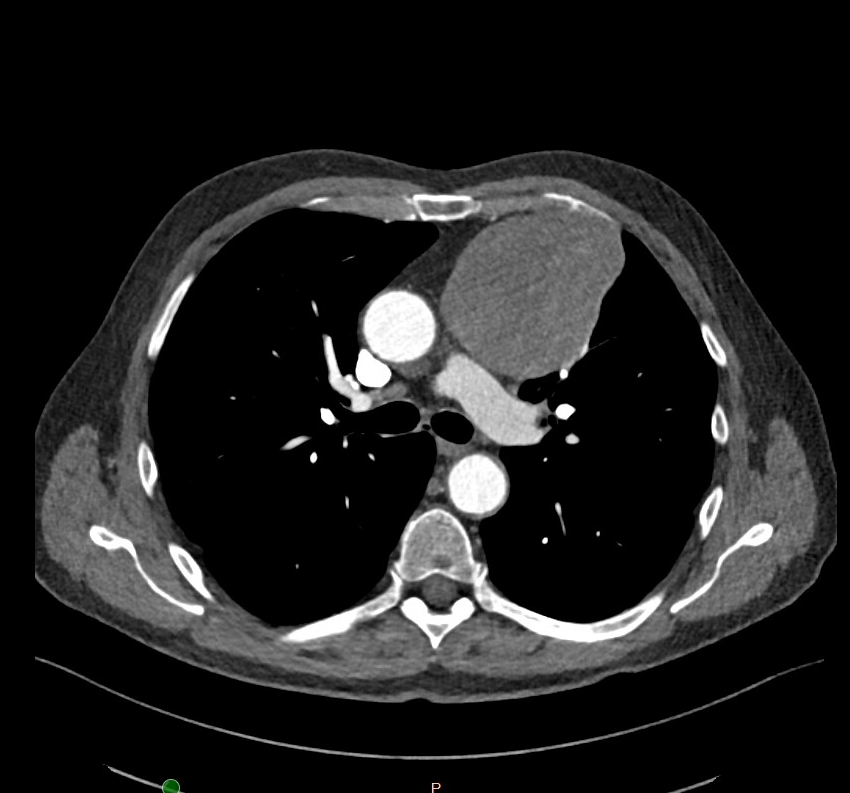

- De arts begint met een gesprek en lichamelijk onderzoek. Bij verdenking op een thymustumor kunnen de volgende onderzoeken worden gedaan:CT-scan van de borstkas: om de grootte en ligging van de tumor in beeld te brengen.